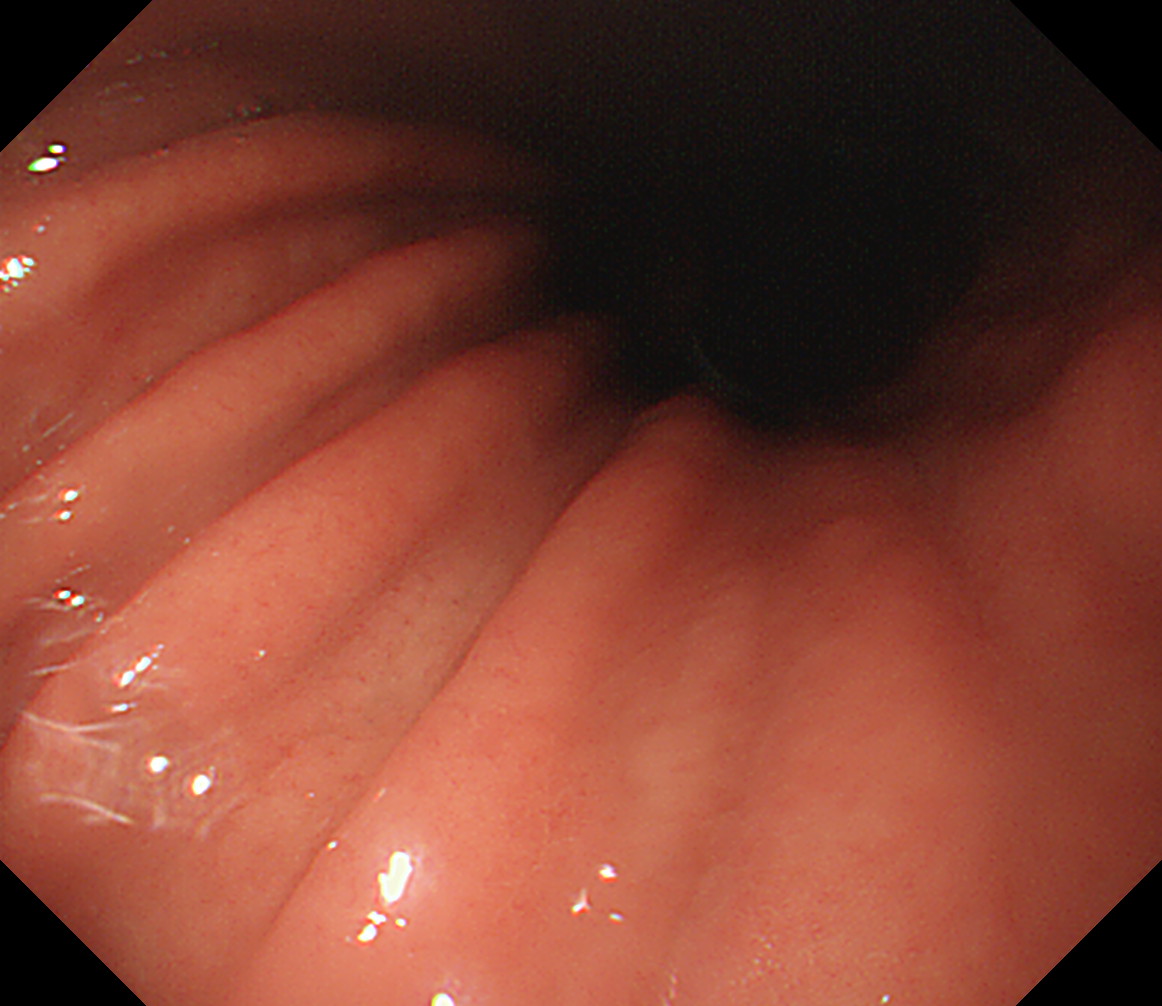

24 体下部後壁 引き上げて

後壁から反時計回り

接線になり見逃しやすい部位です

体下部後壁